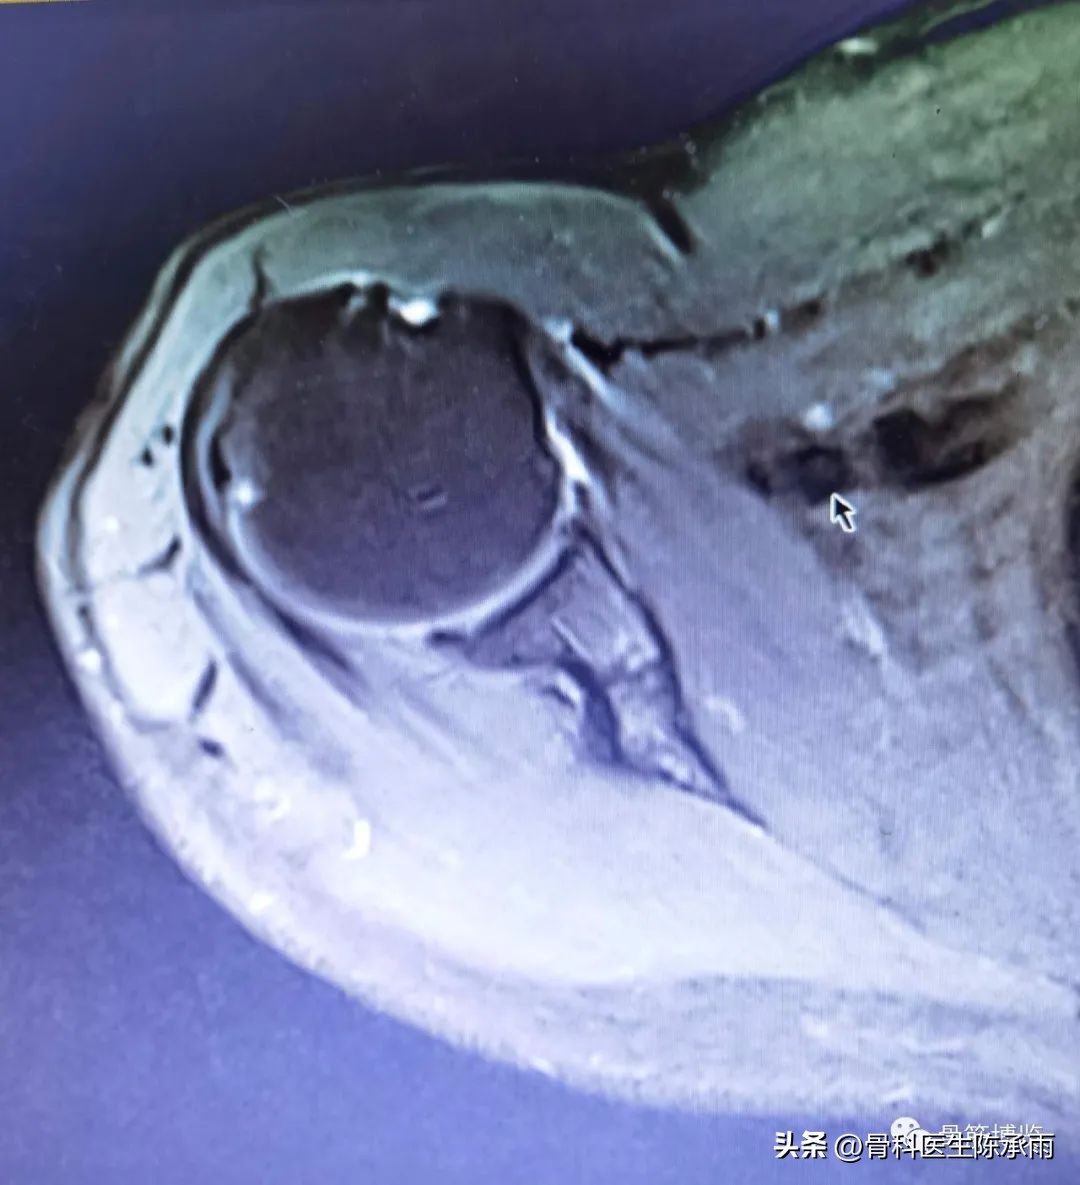

这是1例肱二头肌断裂患者,年轻男性,对上肢外形及力量要求较高

术前影像